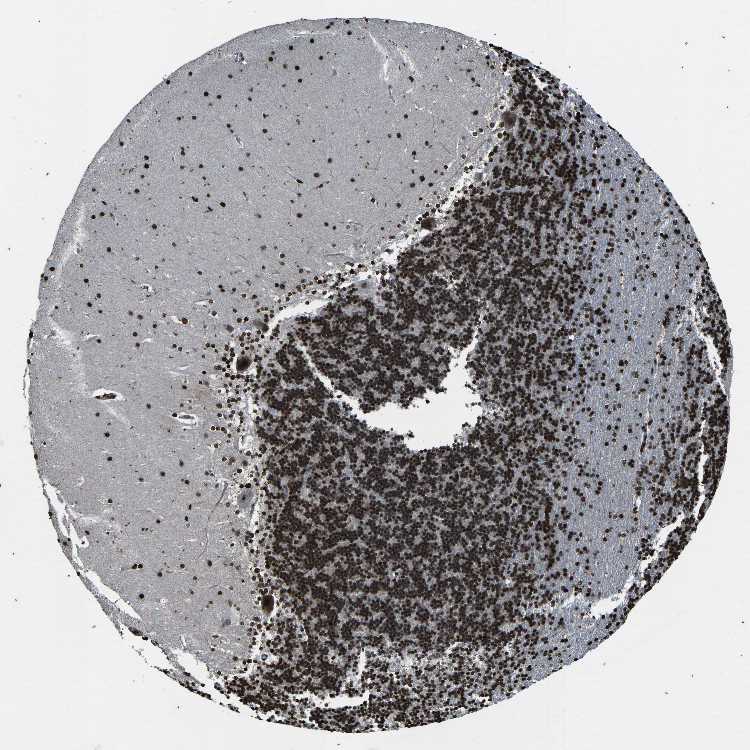

CEREBELLUM - Antibody stainingi

Antibody staining in the annotated cell types in the current human tissue is reported as not detected, low, medium, or high, based on conventional immunohistochemistry profiling in selected tissues. This score is based on the combination of the staining intensity and fraction of stained cells.

Each image is clickable and will lead to virtual microscopy that enables deeper exploration of all samples and also displays staining intensity scores, fraction scores and subcellular localization as well as patient and tissue information for each sample.

Antibody HPA042201Antibody CAB021887

Purkinje cells Not detectedMedium

Cells in granular layer LowHigh

Cells in molecular layer MediumHigh